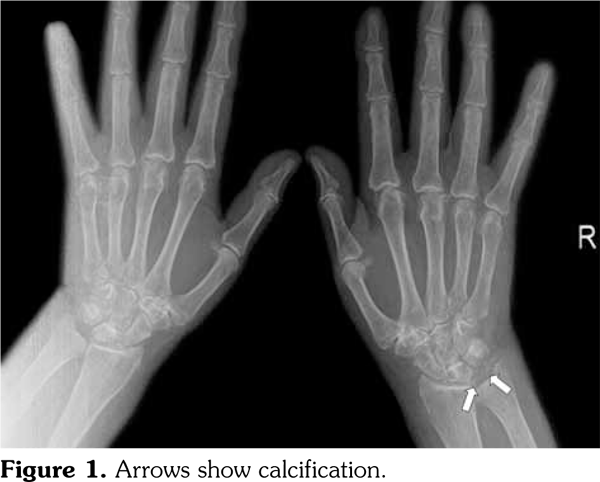

1.3 mg/dL (normal >1.8 mg/dL). On wrist X-ray, there were cystic lesions on carpal and metacarpal bones, and calcification at triangular cartilage localization (Figure 1). Musculoskeletal ultrasonography (USG) of the wrist joint was performed. Effusion was detected at radiocarpal joint on gray scale USG and active synovitis were detected on power Doppler USG. CPDD of the wrist was diagnosed. Prednisolone 5 mg/day and oral magnesium were initiated and furosemide was stopped. Thirty milligrams triamcinolone acetonide was injected into the radiocarpal joint with USG guidance. On the third day of treatment, swelling regressed and pain resolved.